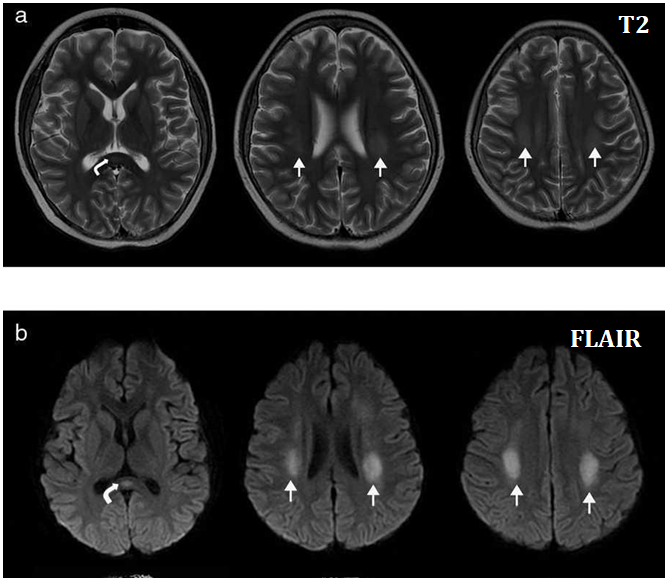

El diagnóstico de neurotoxicidad por MTX se establece mediante una clínica compatible asociada a una historia de administración de metotrexato y una neuroimagen con hallazgos sugestivos. La RM cerebral es la prueba de elección, se caracteriza por una alteración en la señal de la sustancia blanca afectada que aparece como áreas hiperintensas en las secuencias de TR largo (T2, flair) y que causa restricción en las secuencias de difusión.